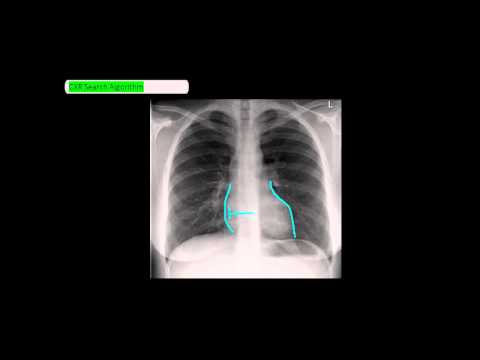

2. Chest X-Ray (CXR) Analysis in a Nutshell :

how to read chest x ray

10. Radiology Basics - How to read a chest x ray ? :

11. Chest X-Ray Reading Method - ABCDE [UndergroundMed] :

16. CXR - How to read the chest x ray - Part I: Concepts and Quality :